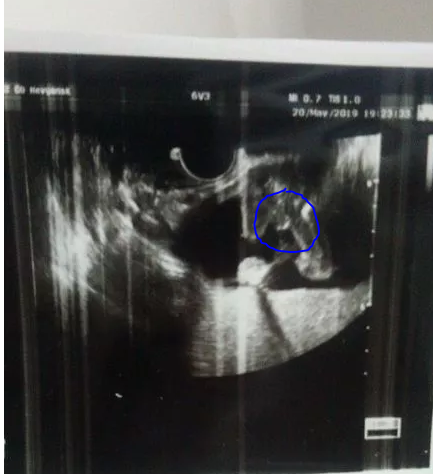

Кто это мальчик или девченка

Девочки подскажите где врач увидела яички и писюн

Вроде как - вот, но мальчик ли??

а где тут вообще ребенок